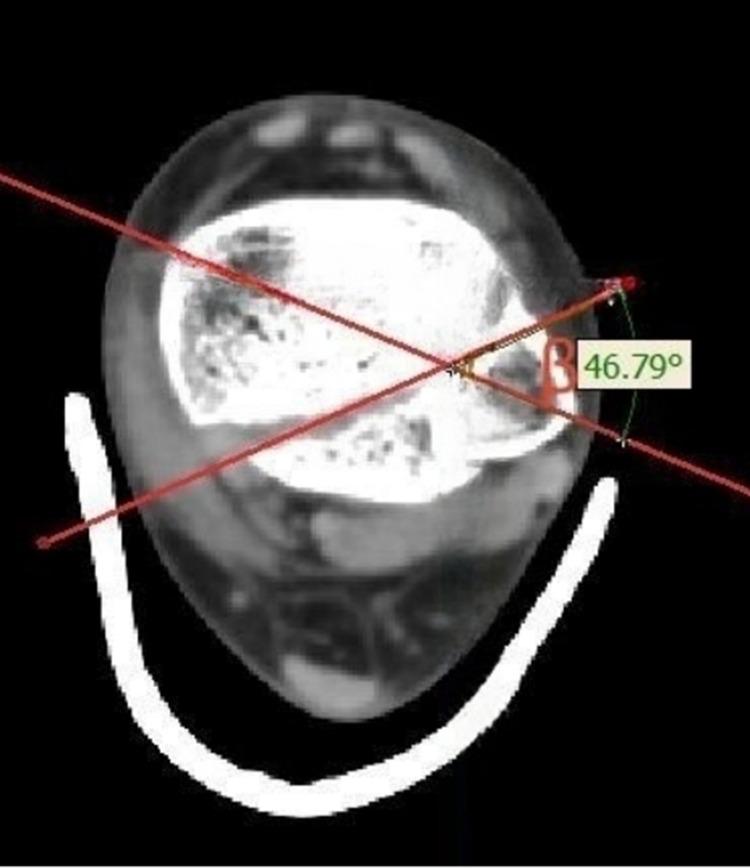

CT scan was performed in105 fractures diagnosed with OTA/AO type 43C pilon fractures between January 2017 and December 2022. Three-dimensional pilon fracture maps were created and converted into fracture heat maps. CT scan graphic parameters including the fracture line height, α angle, β angle, the ratio of the area and size of bone fragment represented by the fracture line to the total articular surface were measured.

方法